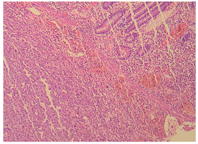

例1患者肿瘤细胞排列呈片状、索条样及网状,或形成交通状的血窦网,位于肠壁全层。瘤细胞呈上皮样,大小比较一致;核呈圆形、卵圆形或梭形,细胞核大、淡染;部分细胞核可见小核仁,异型性明显,核分裂像易见(图2,图3图4);间质伴灶片状出血。与2年前左大腿外侧及左侧腹股沟EA肿瘤组织学相似(图5)。

例2患者上皮样肿瘤细胞呈实性片状排列,位于黏膜下、肌层及浆膜层。瘤细胞呈圆形及卵圆形,核大淡然,异型性更明显;可见大红核仁,局部可见血窦及血管网结构;间质可见慢性炎细胞浸润(图6,图7图8)。与1年前左肺上叶EA肿瘤组织学结构类似(图9)。